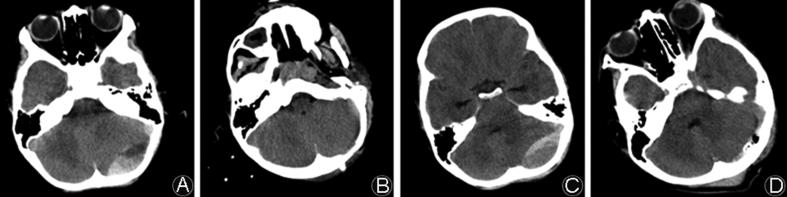

Posterior fossa epidural hematomas (PFEDH) are uncommon in children but usually require timely surgical intervention due to the risk of life-threatening brainstem compression. We attempt to make the surgical procedure less invasive by treating selected pediatric patients with trephination mini-craniectomy.

During this period, a total of 17 patients were surgically treated for PFEDH and 7 were managed with trephination mini-craniectomy for hematoma evacuation. The outcomes were good in all 7 patients as evaluated with Glasgow Outcome Score. There was no mortality in this series. The on average 30-month clinical follow-up showed that patients experienced satisfactory recoveries without complications.

Our results suggest that trephination mini-craniectomy is a safe surgical technique for selected PFEDH patients with moderate hematoma volume and stabilized neurological functions. However, standard craniectomy is recommend when there are rapid deteriorations in patients' neurological functions or the hematomas are large and exerted severe mass effects.